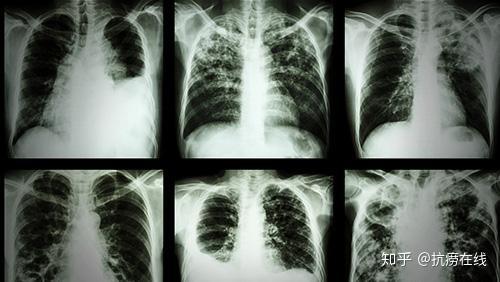

肺结核到底有多恐怖,即使完全消灭结核菌,也不能治回完好的_肺结核